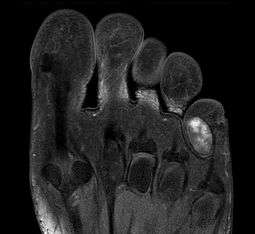

Chondroma of the soft parts located in the little toe.

Extraskeletal chondroma (also known as "Chondroma of soft parts") is a cutaneous condition, a rare benign tumor of mature cartilage.[1]